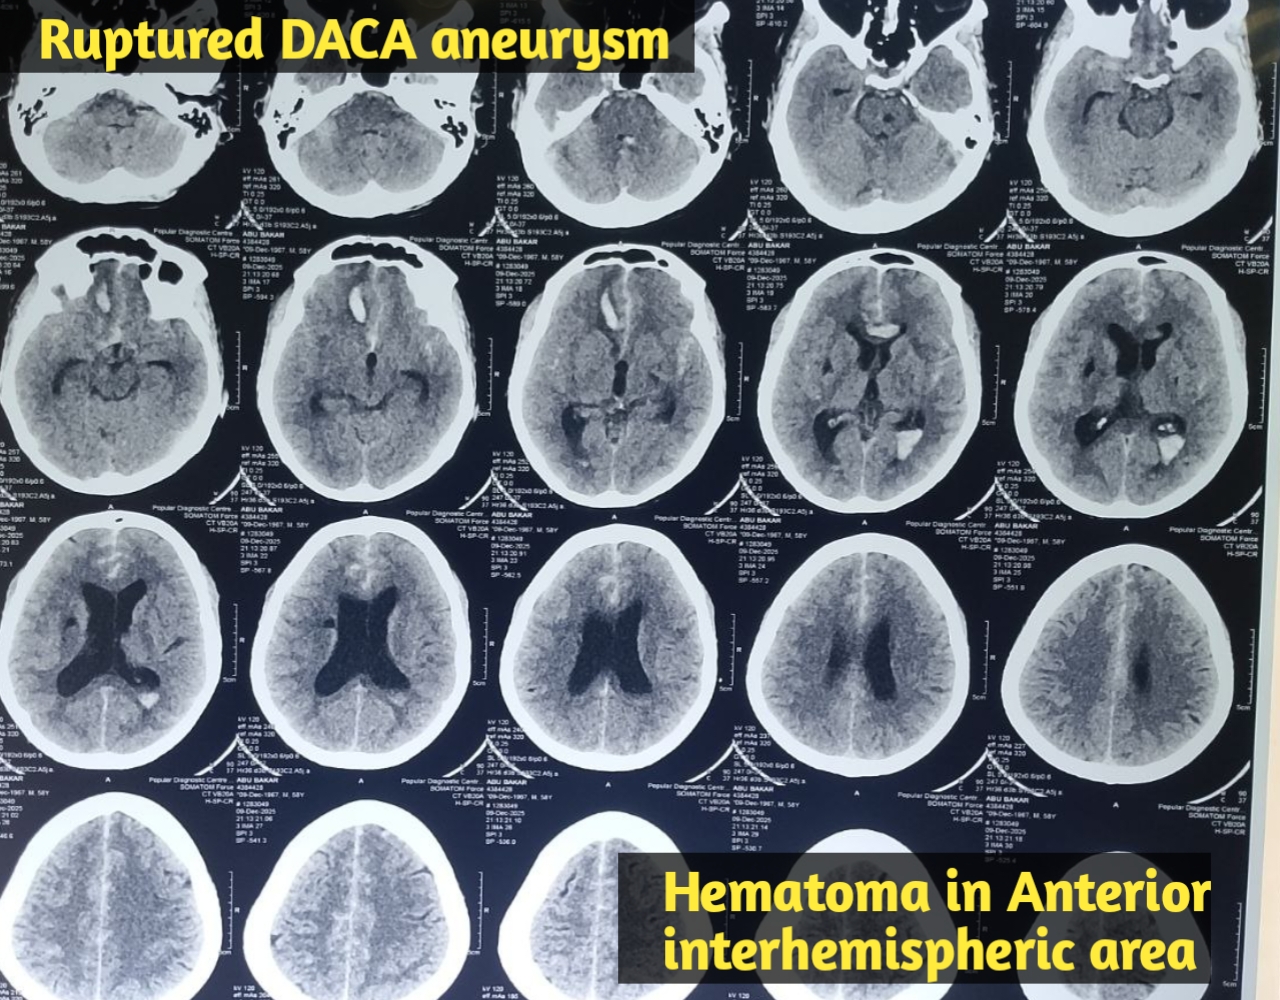

মাথা ব্যথা, ঘাড় ব্যথা, কোমর ব্যথা, পিএলআইডি সমস্যা, হেড ইনজুরি , স্পাইন ইনজুরি , স্পাইনের রড-স্ক্র ফিক্সেশন, মস্তিষ্ক - স্নায়ু - মেরুদণ্ড ব্যথা, স্পাইনাল টিউমার, ব্রেইন টিউমার, প্যারালাইসিস বা পক্ষাঘাত, স্ট্রোক, হাত - পায়ে ব্যথা, হাতে পায়ে ঝিমঝিম ভাব , শিশু নিউরোসার্জারি , ভাসকুলার নিউরোসার্জারি বিশেষজ্ঞ ও নিউরোসার্জন।